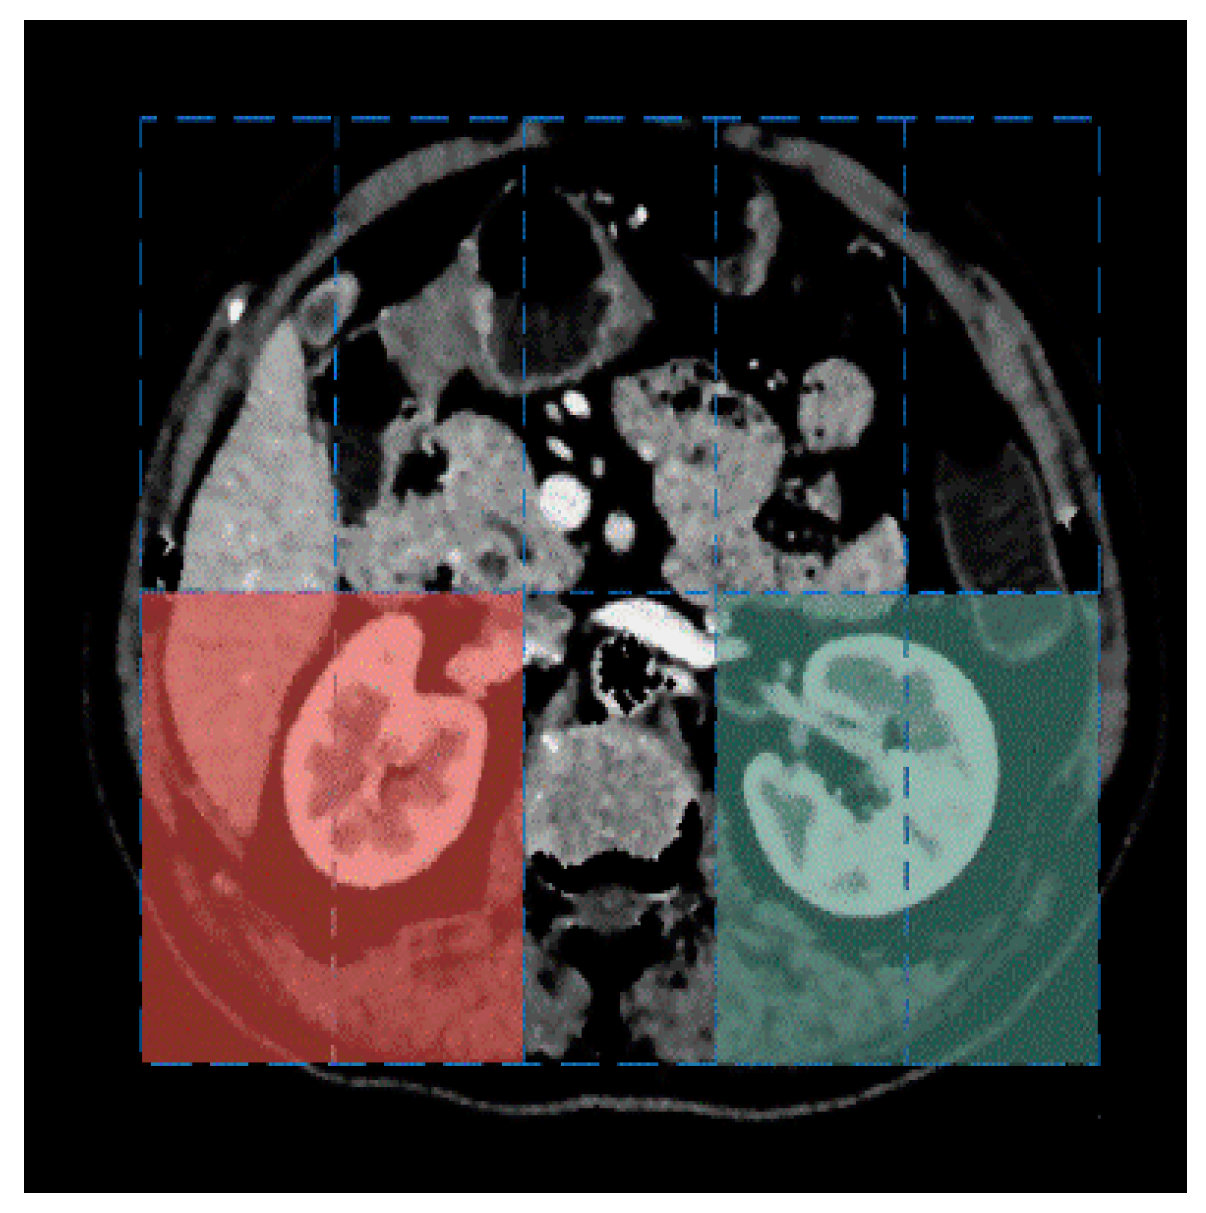

The final set of peaks was obtained after collecting the peaks of all the volume histograms, such that they are used as the K-mean centers for the entire abdominal CT sequence. The clustering process utilizes the Euclidean distance as the similarity measurement and the resulting clustering is depicted in Figure 4. Our adaptive clustering algorithm ensures that the kidneys are always assigned to the brightest cluster, thanks to the preprocessing step that removes the spine and ribs.

Figure 4. Cluster result based on multi-region volume histograms. (a) Original abdominal CT image. (b) Cluster result.